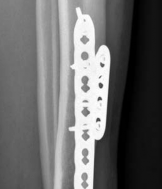

Biomechanically, the transition from the rigid diaphysis to the cancellous metaphysis creates a stress riser. When utilizing plate osteosynthesis for a fracture extending from the shaft into the plafond, the construct must fulfill two distinct biomechanical roles: absolute stability at the articular surface and relative stability along the multifragmentary diaphysis. Absolute stability of the articular block is achieved through anatomic reduction and interfragmentary compression using lag screws. This reconstructs the joint and provides a solid foundation.

Image

Once the articular block is reconstituted, the plate acts as a bridging construct across the zone of metaphyseal and diaphyseal comminution. Locking plate technology is paramount in this region. The locking screws provide angular stability, functioning as an internal fixator that does not rely on friction between the plate and the underlying periosteum. This preserves the extraosseous blood supply, which is vital for secondary bone healing via callus formation. The working length of the plate must be optimized to allow for micromotion at the fracture site, promoting robust enchondral ossification while preventing catastrophic hardware failure.